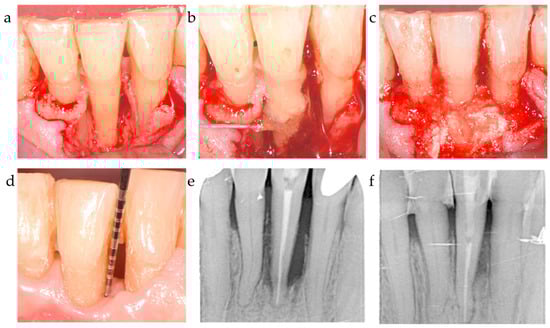

Figure 4.

Center 3 showcase: (a,b) PPD and defect extension; (c,d) defect grafting at surgery as result of barrier placement and xHya application, and clinical outcome at 12-month exam. (e,f) radiographically observed change in bone level around tooth 21 before surgery and 12 months post-op.

The ∆CAL comparison between centers favored center 2 vs. center 1 with a p = 0.006; the difference between C2 and C3 was statistically non-significant (p = 0.718). The radiographic bone fill was significantly greater in patients from centers 2 and 3 vs. center 1 (p = 0.003 and =0.014, respectively) (Table 4). The difference in radiographically documented defect fill between C2 and C3 was statistically non-significant (p = 1.0). As corroborated by the 12-month results, both the significant clinical attachment gain and radiographic alveolar bone improvement remained constantly unaltered during the observation period (Table 2, Figure 1, Figure 2 and Figure 3). The recession increased from baseline to the 12-month visit by 1.2–1.3 mm on average for center 1 and 3, while center 2 recorded a minimal recession increase of less than 0.5 mm.

Nevertheless, the effectiveness of the chosen material composition proved to result in statistically significant differences from the baseline outcomes each center reported. Looking at the baseline number of bony walls, which were almost alike in all three centers (p = 0.137), the results from center 3 reported for the first time a significant CAL and bone gain accompanying xHyA use without a bone substitute in defects presenting a diminished number of bone walls (i.e., 1.5 on average). Stabilizing the defect via a polymer-derived membrane, the pocket closure effect at the level of a residual 3 mm probing depth was constantly observed after 12 months (93%).

Center 3, on the other hand, did not use any particulate material to avoid an artificial radio-opacity in the defect area and applied a polymer barrier membrane instead. This polymer membrane was shown to significantly improve clinical attachment levels in a variety of clinical studies [41]. In a 6-year observational study, Stavropoulos and Karring showed an attachment-level gain with a PPD improvement of 3.8 ± 1.1 mm and a mean CAL gain of 3.8 ± 1.4 mm observed after 1 year. Within this frame of reference, it appears reasonable to suggest that the inconsistency between C1 and C3 was indeed rooted in the choice of substitute material and the fact that xHya was demonstrated to be an efficient addition to the GTR technique applied by center 3 [42].